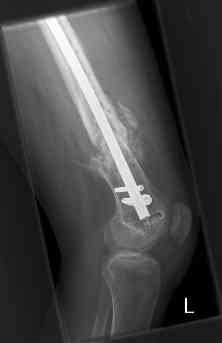

16 yr old boy, high energy motorcycle trauma trauma in July 2005 with:

- hip dislocation + acetabular fracture L

- distal femoral fracture L

- tibial shaft fracture L

- metatarsal fractures L

july 05: LISS femur, LCP plate tibia, double recon. plate post. acetabulum

oct 05: cancellous bone graft femur

aug 06: blade plate + bone graft

nov 06: revision blade plate

feb 07: retrograde nail + bone graft + BMP

may 07: dynamisation nail

sept 07: locking screw removal (max. dynamisation reached)

nov 07: persistant non-union distal femur; other fractures healed uneventfully.

All with gradual/partial weightbearing etc. Currently 50-100% weight bearing, no pain.

Soft tissues are intact. No smoking or diabetes.CRP <2